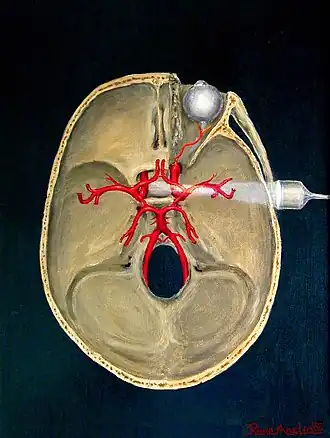

Transcranial

Transcranial Doppler (TCD) and transcranial colour Doppler (TCCD) measure the velocity of blood flow through the brain's blood vessels transcranially (through the cranium). These modes of medical imaging conduct a spectral analysis of the acoustic signals they receive and can therefore be classified as methods of active acoustocerebrography. They are used as tests to help diagnose emboli, stenosis, vasospasm from a subarachnoid hemorrhage (bleeding from a ruptured aneurysm), and other problems. These relatively quick and inexpensive tests are growing in popularity. The tests are effective for detecting sickle cell disease, ischemic cerebrovascular disease, subarachnoid hemorrhage, arteriovenous malformations, and cerebral circulatory arrest. The tests are possibly useful for perioperative monitoring and meningeal infection.[7] The equipment used for these tests is becoming increasingly portable, making it possible for a clinician to travel to a hospital, to a doctor's office, or to a nursing home for both inpatient and outpatient studies. The tests are often used in conjunction with other tests such as MRI, MRA, carotid duplex ultrasound and CT scans. The tests are also used for research in cognitive neuroscience.